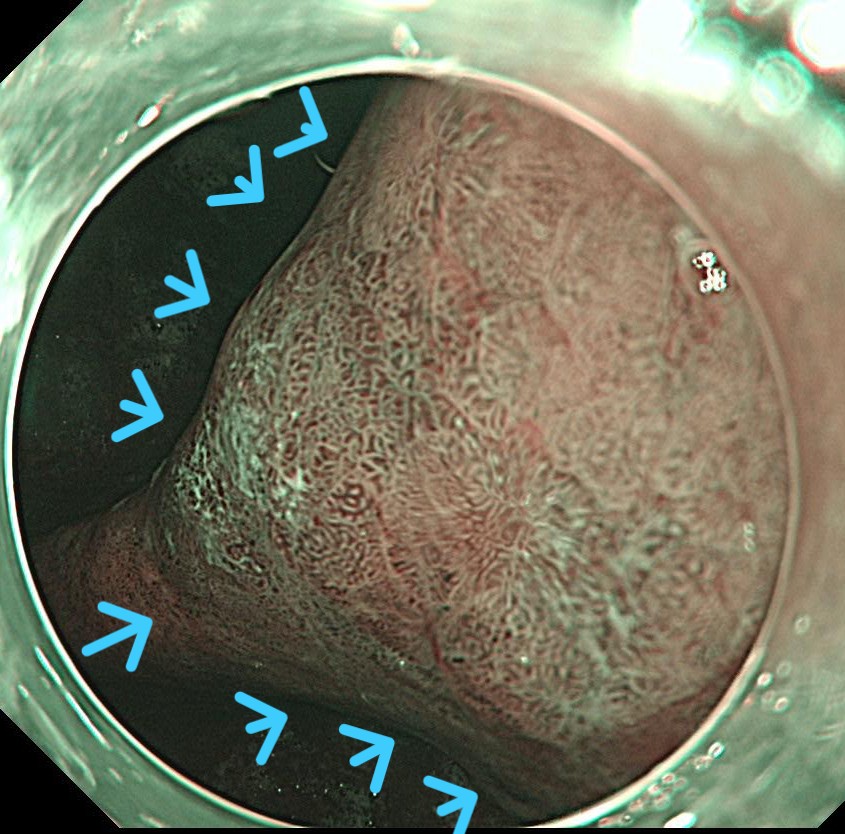

胃角小弯前壁に中心陥凹 周囲隆起するIIA+IIC早期胃がんを認めます。腫瘍径は30mmとやや大きな腫瘍です。

NBI(狭帯域光観察)で腫瘍の不整な新生血管が認識されます。